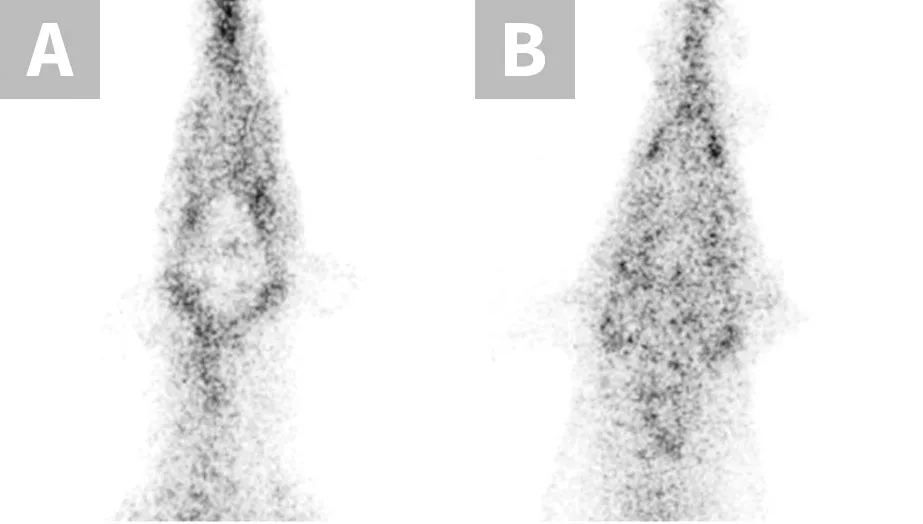

Adverse drug effects caused by the MDR1 gene mutation are not limited to neurologic toxicity. Because P-glycoprotein actively transports substrate drugs into the bile, dogs with the MDR1 mutation have decreased biliary clearance of those drugs normally eliminated via biliary excretion (Figure 2), resulting in increased overall drug exposure.11 Affected dogs experience susceptibility to associated adverse effects when the drugs are administered at recommended dosages. This effect has been documented with vincristine (bone marrow suppression),12 cyclosporine A (immunosuppression),13 doxorubicin (bone marrow suppression, GI toxicity; anecdotal), and others. Affected dogs should receive decreased dosages of these drugs as previously described.14 MDR1 genotyping should be performed to identify at-risk dogs prior to treatment with P-glycoprotein substrate drugs.4

FIGURE 2

Nuclear scintigraphic images of the ventral abdomen of an MDR1 wild-type dog (A) and an MDR1 mutant/mutant dog (B) 2 hours after IV injection of the radiolabeled P-glycoprotein substrate sestamibi (99mTc-sestamibi). P-glycoprotein efficiently pumps 99mTc-sestamibi into the gallbladder in the MDR1 wild-type dog (arrowhead). In stark contrast, biliary excretion is essentially nonexistent in the MDR1 mutant/mutant dog (arrow).